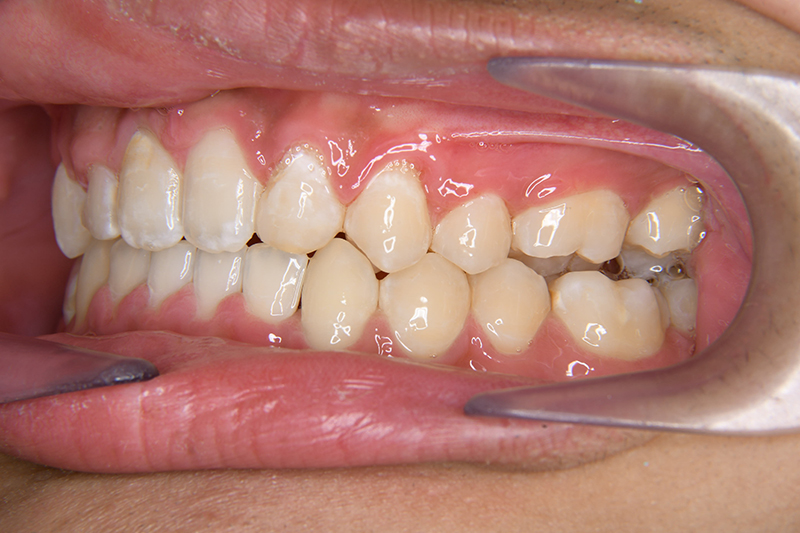

初診時

FP・IOP

主訴 すきっ歯 診断名 上顎右側犬歯先天欠如を伴うアングルⅡ級空隙歯列症例

口腔内所見 over jet 8.0mm、over bite 8.0mmで下顎歯列はスピー湾曲が強く、過蓋咬合、上突歯列、叢生歯列を呈しており、臼歯関係はⅡ級、左側7は鋏状咬合となっていた 。上顎両側2は矮小歯で上顎右側Cは晩期残存をしていた。また上顎歯列は空隙歯列を呈していた。

批評・予后 側貌はconcave typeであり、下顎歯列は叢生が少ないこと、右上3欠損、左右上2は矮小歯であることを考慮して右上C、左側2抜歯とした。治療後はアンテリアレシオの調和を図るべく右上2は暫間的修復(CR)にて歯冠幅径を大きくしている。保定終了後には同部位は最終補綴を装着する予定である。